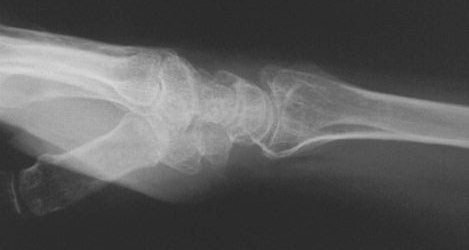

Clinical Example: Distraction plate fixation distal radius fracture

distal radius fracture

distraction plate